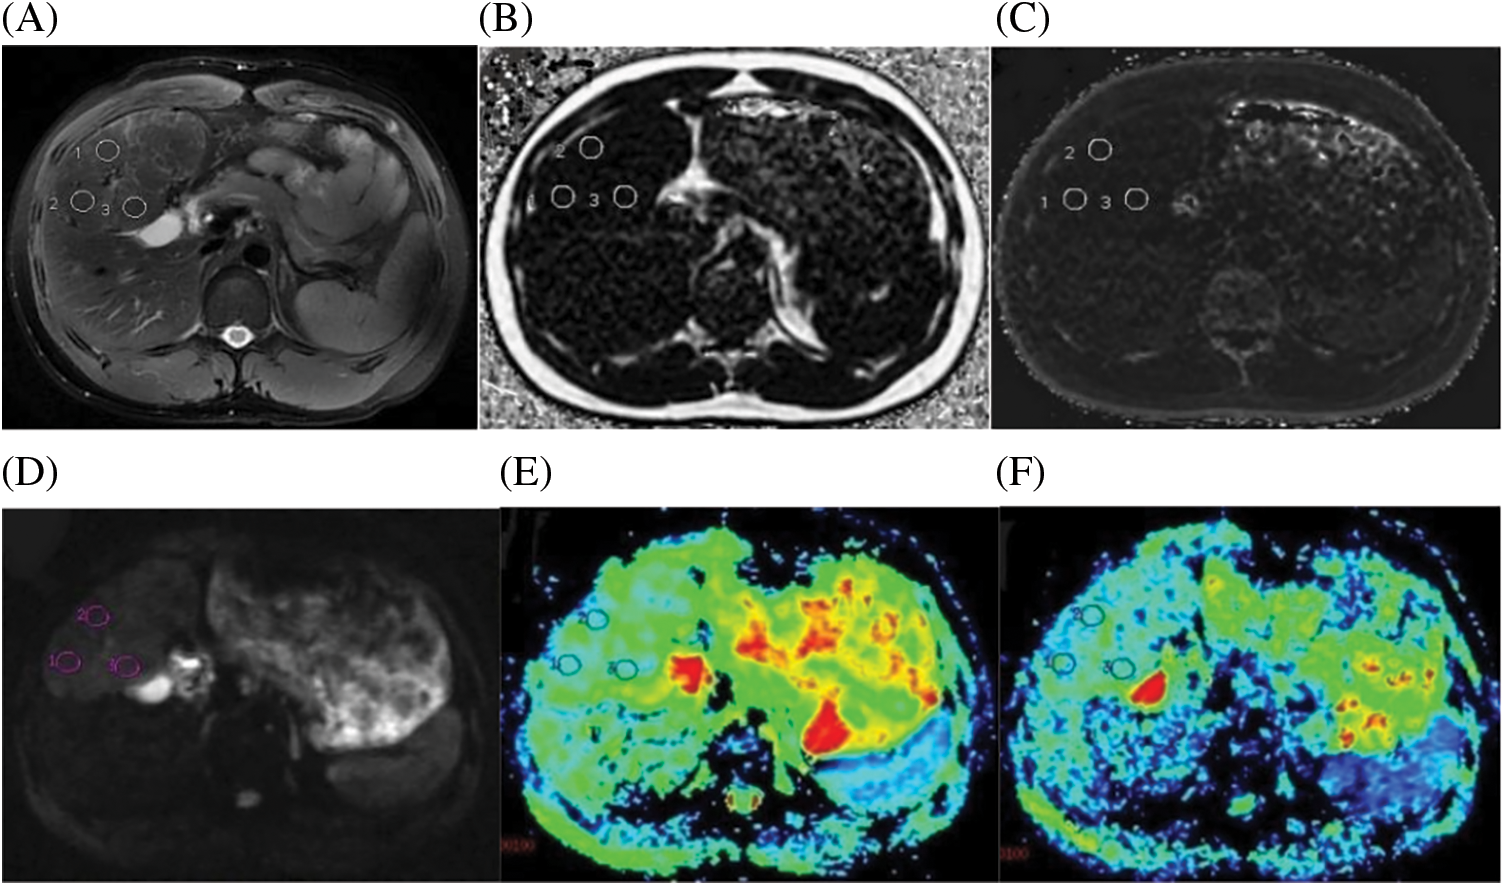

Figure 3: A case of a 21-year-old male with FNH confirmed by histopathology. (A) Axial fat-suppressed T2-weighted unenhanced image showed three circular ROIs with the same size. (B) Fat Fraction(FF) = 2.61%. (C) R2* relaxation rate = 21.68 Hz. (D) IVIM Diffusion-weighted image (b = 0 s/mm2) showing three circular ROIs, according to regular MRI sequences to avoid multiple internal foci of the necrosis area. (E) ADC = 1.45 × 10−3 mm2/s. (F) D = 1.138 × 10−3 mm2/s